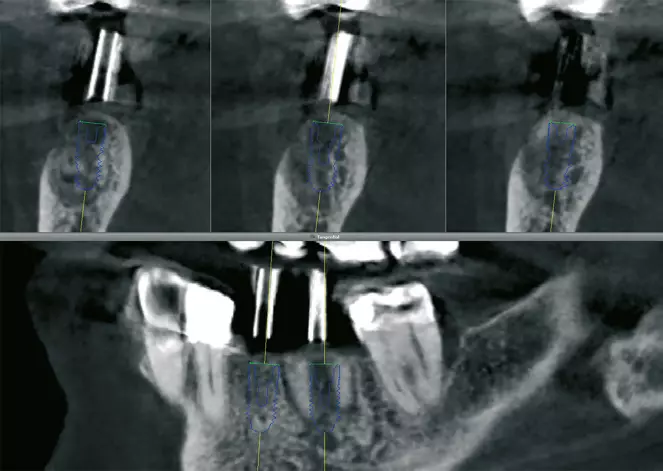

Nach 6 Monaten Einheilzeit wurde die Gitterentfernung mit gleichzeitiger Implantation durchgeführt. Nach Vorbereiten der Patientin und entsprechender Lokalanästhesie wurde eine marginale, entlang an Zahn 34 und der vorhandenen Narbe krestale leicht linguale Schnittführung gewählt. Zur Darstellung des Gitters wurde ein vestibulärer und lingualer Mukoperiostlappen präpariert. Das Gitter zeigte sich regelrecht eingeheilt und zum Teil sogar knöchern bedeckt (Abb. 28). Zur Entfernung des Gitters wurde dieses an der mittleren Sollbruchstelle aufgebrochen und der linguale und vestibuläre Anteil getrennt entfernt (Abb. 29a und b). Anschließend wurde das Implantatlager vorgebohrt und entsprechend dem Bohrprotokoll des Herstellers aufbereitet (Abb. 30). Der Planung folgend wurden dann drei Implantate (Bego SC) regio 35 mit 4,1 x 8,5 mm, regio 36 mit 4,5 x 8,5 mm und regio 37 mit 4,5 x 7mm gesetzt (Abb. 31). Für eine Nachkorrektur der Knochenkontur um die gesetzten Implantate wurde nochmals DBBM eingebracht, mit einer Kollagenmembran (Geistlich Bio-Gide) und PRF abgedeckt und mit einer spannungsfreien Naht verschlossen (Abb. 32 und 33). Das postoperative Röntgenbild zeigt die drei gesetzten Implantate (BEGO SC) an den jeweils vorher digital geplanten Implantatpositionen (Abb. 34).